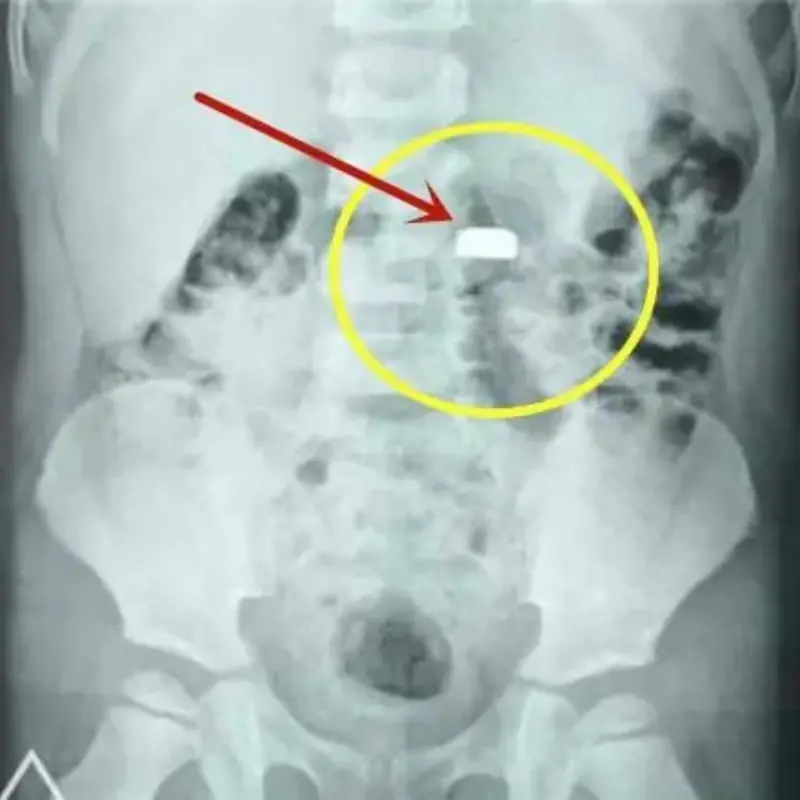

ช็อก เด็ก 3 ขวบกลืนถ่านกระดุม แม่ช่วยทันก่อนอันตราย

เด็ก 3 ขวบกลืนถ่าน แม่แก้ทันด้วยสิ่งนี้ก่อนส่งหมอ!